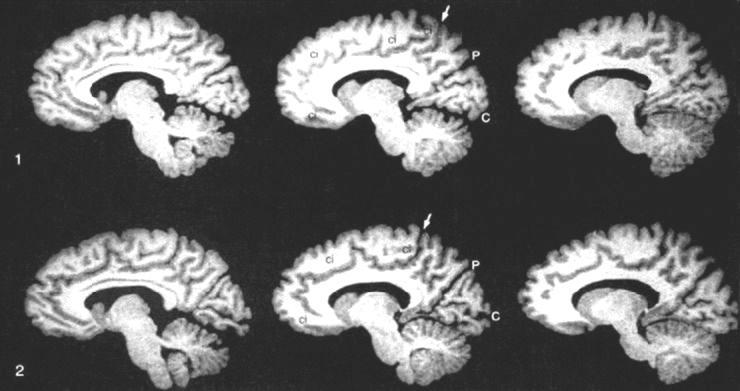

MRI-скан мозга однояйцевых близнецов. Между P и стрелкой у ребенка в верхнем ряду 3 мозговые извилины, а у ребенка в нижнем ряду 4 (Steinmetz H., Herzog A., Huang Y., Hacklander T. Discordant Brain-Surface Anatomy in Monozygotic Twins // The New England Journal of Medicine. 1994.  331. P. 951952). Паттерн мозговых извилин и борозд формируется главным образом в течение трех последних месяцев беременности. Таким образом, причина этих негенетических различий должна возникать именно в этот период.

Конечно, структура нашего мозга и наше поведение определяются не только генетикой. Основанием для различий в характере идентичных близнецов могут быть различия в их мозге, заметные с первого взгляда. Развитие мозга, выраженное в паттерне извилин и борозд, уже во время беременности должно находиться под сильным влиянием негенетических факторов, например несколько иной окружающей среды в матке и локальных процессов самоорганизации. В этих процессах клетки мозга конкурируют за лучшую организацию связей (см. ниже). После рождения обучение также играет роль в возникновении структурных и функциональных различий в мозге, как это следует, например, из профессиональных различий музыкантов и шоферов такси (см. главу XV.2).